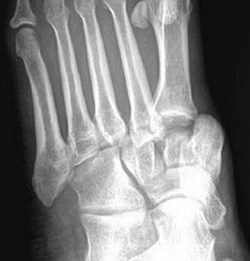

Диагноз устанавливают на основе рентгенограмм в профильной и фасной проекциях. Чтобы избежать ишемических осложнений, диагноз «подтаранный вывих стопы» требует от врача оказания неотложной травматологической помощи. Эта помощь должна учитывать конкретные варианты повреждений подтаранного сустава.

Для уточнения диагноза и выявления сопутствующих повреждений выполняют рентгенографию в двух проекциях. Вывихи, сопровождающиеся повреждением костного и связочного аппарата, считаются тяжелыми. Нормальная функция сустава возможна только при точном восстановлении взаиморасположения отломков.

Подтаранный вывих стопы встречается крайне редко. Он возникает при резком подворачивании стопы и сопровождается разрывом связок, сильной болью, отеком и деформацией. Для уточнения диагноза и исключения переломов проводят рентгенографию.